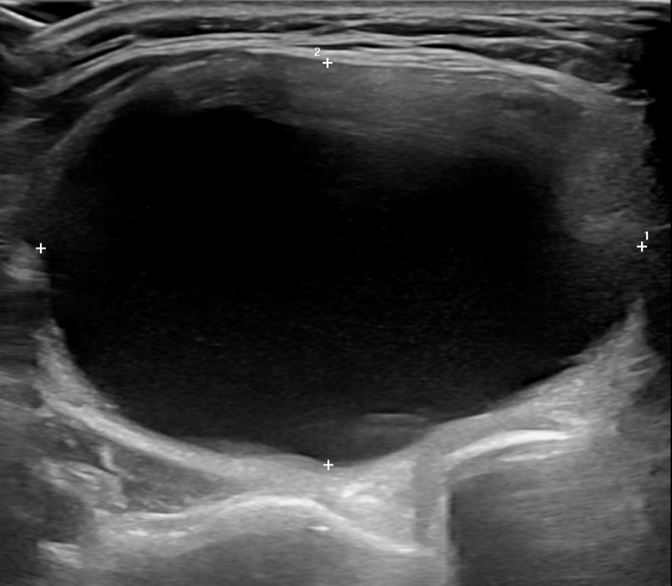

모든 시술 과정은 초음파 유도하에 시행됩니다. 또한, 국소마취만으로 시술이 가능하므로 외래 환자를 대상으로 시행될 수 있습니다. 갑상선 협부를 통해 굵은 주사 바늘을 결절 내부로 삽입하여 가능한 한 많은 내부 액체를 흡인한 후 적당량의 에탄올을 결절 내부로 주입합니다. 시술이 끝나면, 주사 바늘 천자 부위를 5-10분 정도 가볍게 압박합니다.

시술전